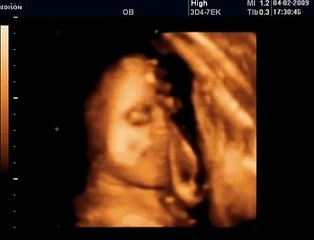

www.cemturan.combr www.dr-cemturan.combr www.jinekolojikonkoloji-istanbul.combr www.perinatoloji-istanbul.combr Hamilelikte renkli Doppler ultrason niçin yapılır? Bebek renkli mi görülür yoksa damarları görmek için mi renkli Doppler yapılır? Prof. Dr. Cem Turan'dan izleyin. Renklli doppler ultrason ile en çok incelenen damar bebeğin göbek kordonundaki damarlardır (umblikal damarlar). Bunun dışında rahim damarları, beyin damarları, kalp damarları gibi çeşitli damarlar incelenebilir. Özellikle rahim içerisinde gelişme geriliği (iugr) şüphesi olan bebeklerde, anomali varlığında, kalp ritm bozukluğu veya kardiyak anomali varlığında, yüksek tansiyon hastalarında yapılır. Her gebelikte rutin olarak yapılan bir inceleme değildir.